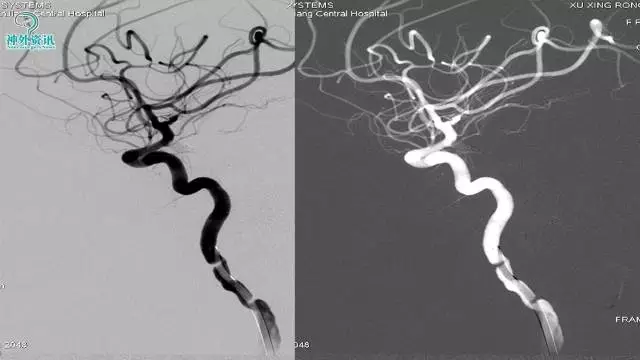

今天为大家分享的是“强生医疗CNV-神经介入专栏”第三十六期,由重庆第三军医大学附属新桥医院神经外科刘俊带来的“Galaxy弹簧圈在不规则动脉瘤中的临床应用”精彩讲课视频及PPT,欢迎观看。文章仅代表作者个人观点,如有不同见解,欢迎同道斧正!